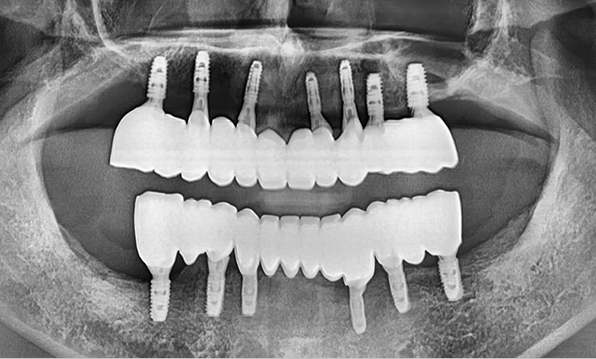

3D 디지털 진단을 통한 체계적인 계획

전체 임플란트는 위턱과 아래턱의 교합, 잇몸뼈의 상태 및

얼굴 변화 등 모든 것을 고려해 식립해야 합니다.

서울더자연치과는 3D 디지털 기술의 정밀 진단을 바탕으로

수술 계획을 세워 수술을 집도합니다.